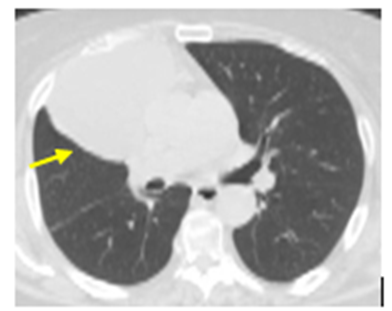

We report a case of a 64-year-old lady, who presented with clinical features suggestive of intestinal occlusion due to volvulus, with an incidental finding of a giant pericardial cyst in the right cardiophrenic angle, measuring approximately 10.9 cm x 9.7 cm x 9.8 cm (Figure. 1).

Figure 1. Incidental finding of a giant pericardial cyst (yellow arrow)